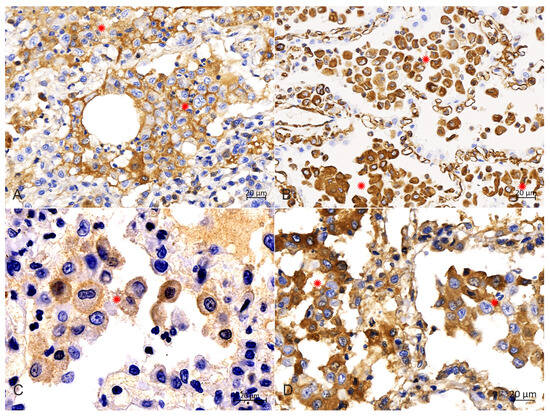

Background: Feline pulmonary Langerhans cells histiocytosis (PLCH) is a rare disorder that results in progressive respiratory failure secondary to pulmonary parenchymal infiltration with Langerhans cells (LCs). A diagnosis of PLCH is proposed based on the clinical features and pathological findings and confirmed based [...] Read more.

Background: Feline pulmonary Langerhans cells histiocytosis (PLCH) is a rare disorder that results in progressive respiratory failure secondary to pulmonary parenchymal infiltration with Langerhans cells (LCs). A diagnosis of PLCH is proposed based on the clinical features and pathological findings and confirmed based on the infiltrating histiocytic cells. There are few documented cases of feline PLCH, and this case report of PLCH in an African Lion could present new information and aspects of this feline histiocytic disease. Case presentation: An African lion at Hohhot Zoo showing severe hyporexia and dyspnea with subsequent mental depression and emaciation died of exhaustion after a 35-day course of illness. Empirical treatment did not have a significant effect. An autopsy revealed that the lungs were enlarged and hardened due to infiltrative lesions, with many yellowish-white foci in all the lobes and sections. Furthermore, the kidneys were atrophied and had scattered grayish-white lesions on the surface. At the same time, congestion was widely distributed in various locations, including the liver, subcutaneous loose connective tissues, serosal surface and other tissues and organs. Histologically, proliferative histiocytic cells (PHCs) were scattered in the alveolar cavities, bronchioles and submucosa of bronchioles, with evident cellular and nuclear pleomorphism, and thus the alveolar septa were obliterated. The histopathological changes in other organs included chronic sclerosing glomerulonephritis, proliferated Kupffer cells in the liver, adrenal edema and interstitial connective tissue hyperplasia, as well as atrophy of the small intestines and spleen. Furthermore, immunohistochemical analysis results were strongly positive for CD1a, vimentin, S100 and E-cadherin in the membrane or cytoplasm of PHCs, supporting an LC phenotype. Conclusions: Here, we present a rare pulmonary Langerhans cell histiocytosis case in an African lion. Full article